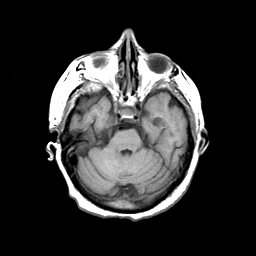

Basal Ganglia Calcification: T1-weighted MR -- Slice #5

[Home][Help][Clinical] Slice 5